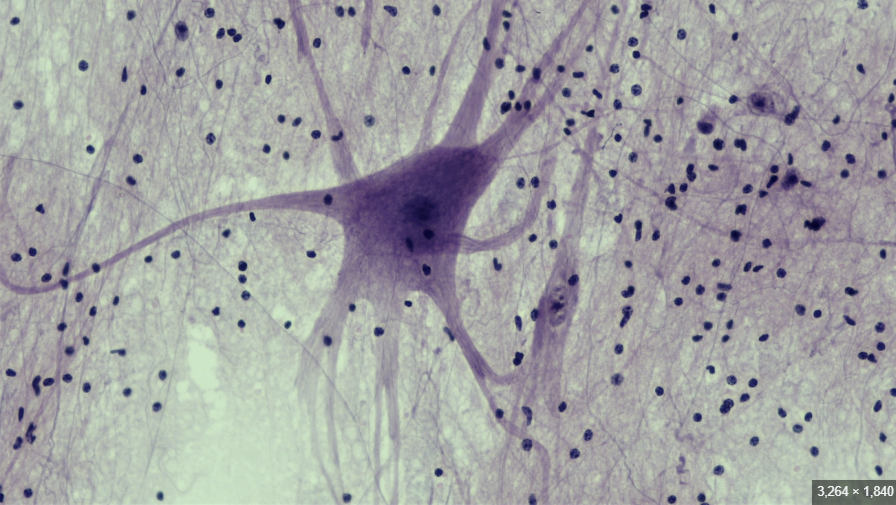

Nervous Tissue

knowt flashcard image